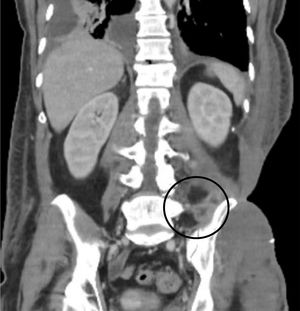

La evolución inicial fue desfavorable; la necrosis en flanco continuó progresando, y el paciente presentó shock séptico que requirió la administración de vasoactivos y ventilación mecánica invasiva. Una tomografía computarizada (TC) mostró signos de miositis grave afectando a musculatura en flanco y glúteo izquierdo.

Después de un mes de ingreso y tras conseguirse la negativización de los cultivos, se inició la cobertura del defecto con injertos de piel autóloga parcial mallados, de manera exitosa (fig. 4). En total se realizaron 6 cirugías de desbridamiento y 2 de cobertura por parte de Cirugía Plástica. Tras 50 días de estancia en la Unidad de Cuidados Intensivos, el paciente pudo trasladarse a planta de hospitalización convencional. Tras la estabilización de la zona cutánea y subcutánea, se observó persistencia de colecciones subyacentes a pala iliaca izquierda, que se comportaban por TC como abscesos (fig. 5). Fue imposible su drenaje ecoguiado dada la situación desepitelizada de la zona, que contraindicaba el acceso percutáneo. Las pruebas de imagen resultaron contradictorias: una gammagrafía con leucocitos marcados no sugería infección activa, pero una resonancia magnética (RM) resultó compatible con abscesos de partes blandas en músculo cuadrado lumbar, ligamento ilio-lumbar y músculo iliaco izquierdos, con datos de osteomielitis en sacro y hueso iliaco. Por ello, se decidió realizar pauta prolongada de posaconazol oral (300mg/día). En el día 66 de ingreso, el paciente fue dado de alta. El tratamiento con posaconazol se prolongó 6 meses, sin presentar efectos adversos. Pasado ese tiempo se realizó nueva RM, evidenciándose marcada mejoría radiológica, con disminución de las colecciones de la musculatura adyacente la articulación sacroiliaca izquierda y sin datos concluyentes de osteomielitis, por lo que se decidió suspender el tratamiento. Tres meses después de la suspensión del posaconazol, el paciente se encuentra asintomático, con el defecto de cobertura cutánea solucionado y sin signos de recidiva de la infección (fig. 4).